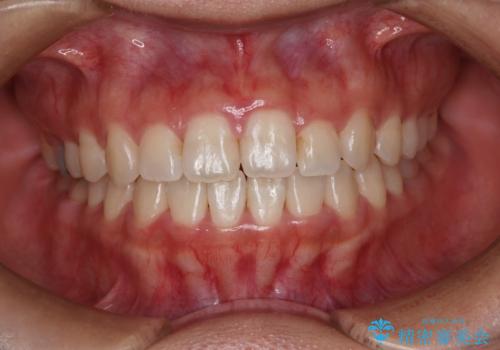

[マウスピース矯正] がたがたの歯並びをきれいにしたい

![[マウスピース矯正] がたがたの歯並びをきれいにしたいの症例 治療前](https://seimitsushinbi.jp/wp/wp-content/uploads/2025/06/0d238550c8a0fddc4de7b2c337c6c786-500x350.jpg?v=1750323380)

![[マウスピース矯正] がたがたの歯並びをきれいにしたいの症例 治療後](https://seimitsushinbi.jp/wp/wp-content/uploads/2025/06/IMG_0002-2-500x350.jpg?v=1750323305)